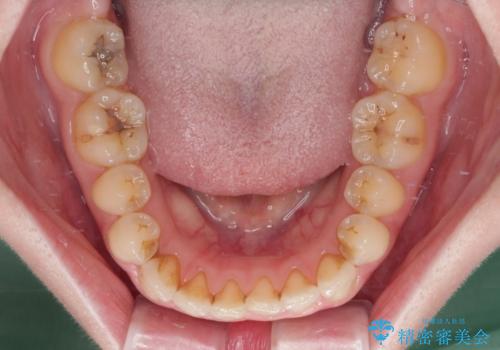

- 奥歯の銀歯をセラミックにしたいとのことで来院された患者様です。

当初は奥歯のみの治療をご希望でしたが、話を進めていくうちに、軽度ではあるものの、幼少期の薬の影響で歯が変色していることがコンプレックスであるということが分かりました。

長年歯の色が塞ぎ込んでいた部分があるとのことで、これを機会に全ての歯を真っ白にするために、オールセラミッククラウンにて補綴治療を行うこととしました。